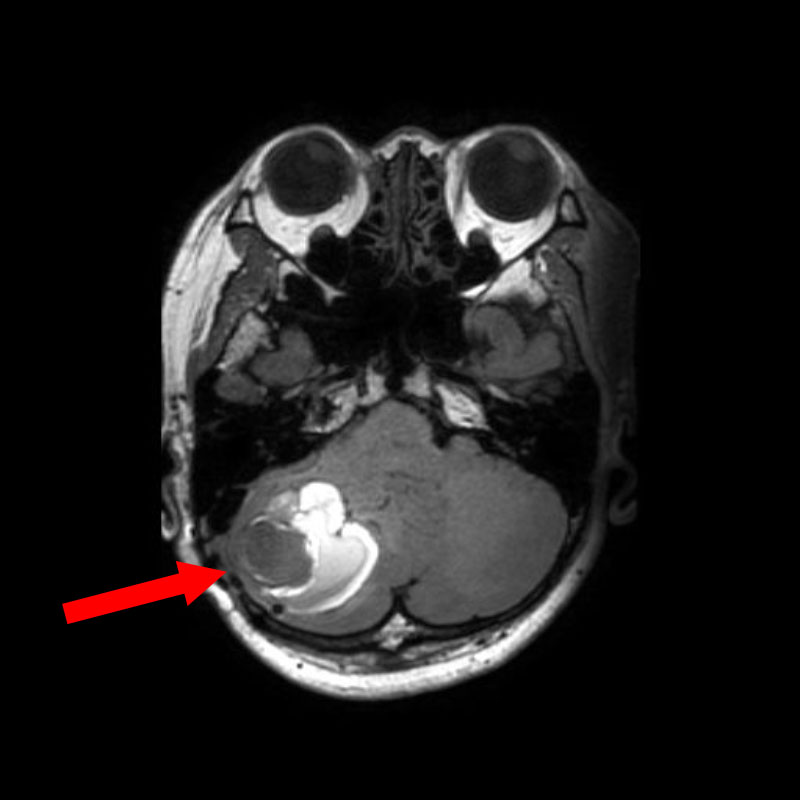

684

'25年10月

50代

右小脳静脈性血管腫

頭蓋内腫瘍摘出術

No.’25_86 手術前1

No.’25_86 手術前2